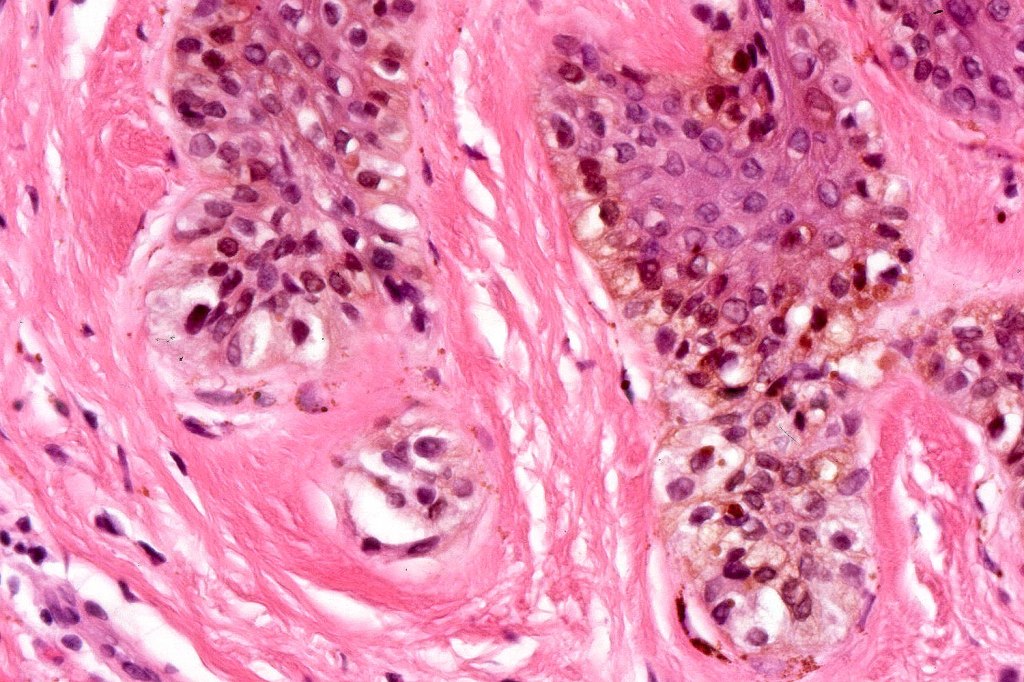

Histological features

•Large dyscohesive nests with retraction artifact, not restricted to the tips of the epidermal ridges

•Heavy pigmentation (sometimes gray/green)

•Bridging common, often over multiple rete ridges

•Dermal fibrosis (sometimes lamellar)

. HMB45 shows gradation with depth, Ki67 is low